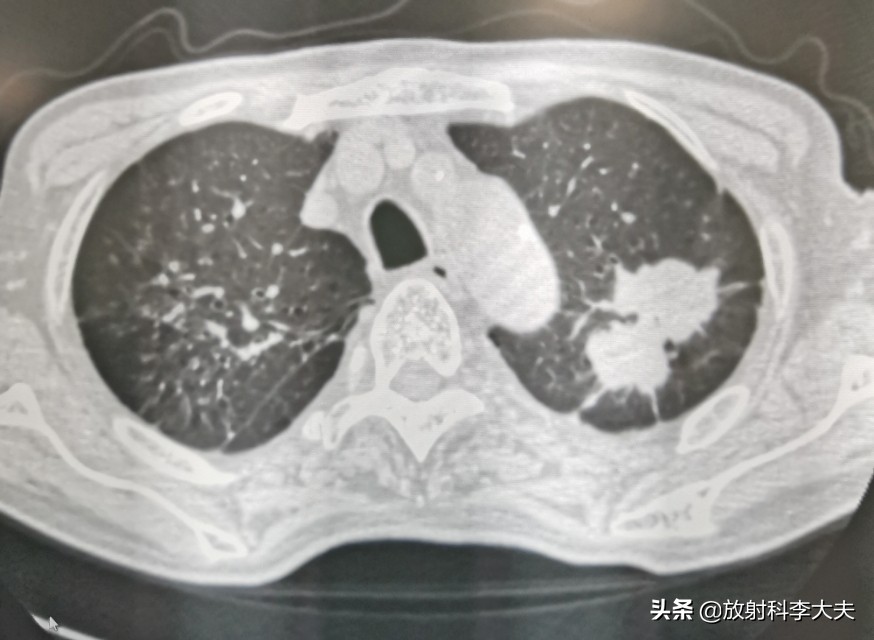

双肺多发的病灶,有的已经钙化,陈旧的结核灶。但是,左肺上叶一个哑铃形状的病变,引起重视。

左肺上叶病变可见分叶,尖后段支气管欠通畅。影像上考虑有肺癌的可能,但是鉴于有肺结核病史,还需要慎重考虑。

病人回家吃了两个月的抗痨药,四月份回来复查。

哑铃长大了,分叶征更明显了。两个月的时间,病变增大,说明抗结核无效,基本上排除结核,肺癌可以考虑了。